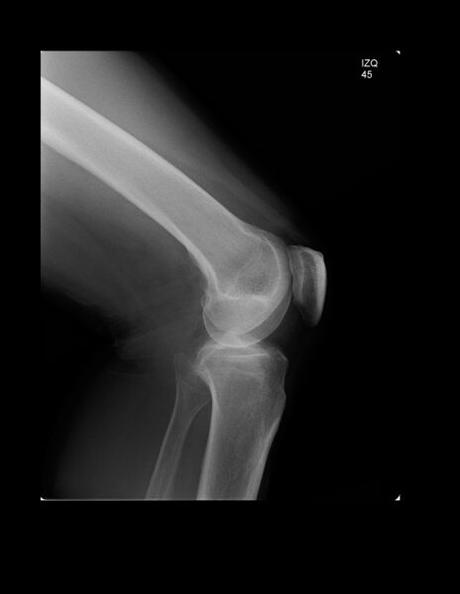

RADIOGRAFIA AP Y LATERAL DE RODILLAS

LAS PROYECCIONES RADIOLÓGICAS MUESTRAN LOS SIGUIENTES HALLAZGOS:

Los tejidos blandos de ambas rodillas, sin evidencia de alteraciones.

Las estructuras óseas de ambas rodillas; fémur distal, peroné y tibia proximal y rotula con adecuada mineralización, sin evidencia de fractura.

Espacio articular femorotibial de ambas rodillas, con adecuada amplitud.

Espacio articular trocleo-rotuliano de ambas rodillas, con disminución de su amplitud.

Rotula derecha, con ángulo de Muñoz de -10.1°, índice de install y Salvatti de 0.99.

Rotula izquierda con ángulo de Muñoz de -9.6 °, índice de Insall-Salvati de 0.85.

OPINIÓN RADIOLÓGICA:

EN EL PRESENTE ESTUDIO RADIOGRÁFICO, AMBAS RÓTULAS, CON DESPLAZAMIENTO LATERAL, ADEMÁS ROTULA IZQUIERDA CON DESPLAZAMIENTO INFERIOR.

DISMINUCIÓN DE LA AMPLITUD DEL ESPACIO TRÓCLEO ROTULIANO DE AMBAS RODILLAS, SUGERENTE DE CONDROMALACIA PATELAR.

CORRELACIONAR CON DATOS E HISTORIA CLINICA DEL PACIENTE